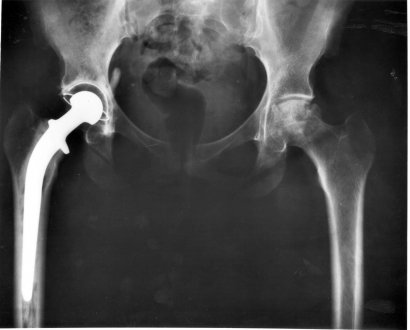

Les traumatismes médullaires sont parmi les principales causes de paraparésie ou de paraplégie aiguë. Dans ces cas-là, il faut examiner l’animal afin de détecter d’éventuels dommages. L’opération chirurgicale reste la meilleure option afin de traiter ce genre de pathologie.

Bien qu’il existe des traitements sans opération chirurgicale agressive, en général, le résultat n’est pas très probant. En effet, ils ont tendance à causer des micros fractures au niveau du disque et donc à empirer la situation. Un problème d’origine vasculaire ou une infection localisée au niveau de la zone médullaire peut également causer une certaine faiblesse dans le train postérieur voire même de la paraplégie.